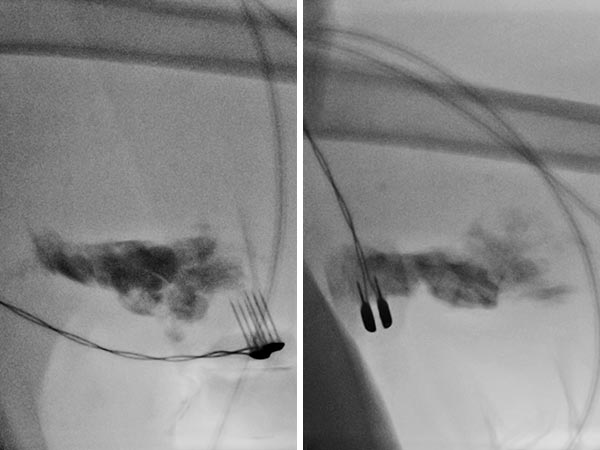

Durchleuchtung während Elektrosklerotherapie nach Injektion von 0,75 mg Bleomycin mit 2,5 ml Kontrastmittel in die lymphatische Malformation. Applikation der Stromimpulse mit der Fingerelektrode.